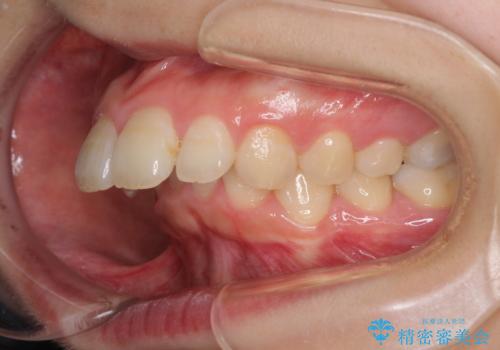

- 飛び出した上顎前歯を気にして来院された患者様です。

下顎は左右2番目の歯が2本欠損しており、上下前歯の前後的な位置は著しくずれている状態でした。

骨格的にも上顎骨が前突傾向にあり、極端な過蓋咬合になっていました。

強い咬合力に抵抗するように歯を動かす必要があるにもかかわらず、上顎第一大臼歯が1本欠損しているため、治療は困難を極めることが予想されました。